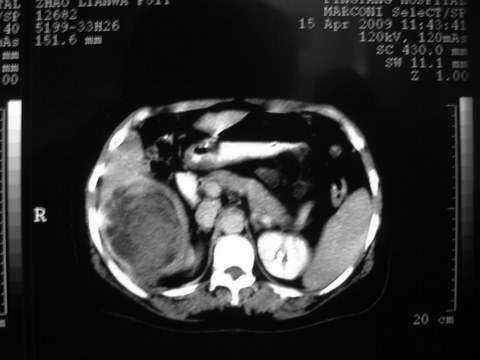

患者 女 51岁 两天前感觉上腹疼,无明显诱因,b超示肝右叶囊实性占位,边缘清楚,其内回声不均匀,ct增强如图,大家看看是什么 ,病人一年前及两月前b超检查只是提示胆囊炎

外院术后,证实肝癌合并出血

出病理 中分化肝细胞癌合并出血